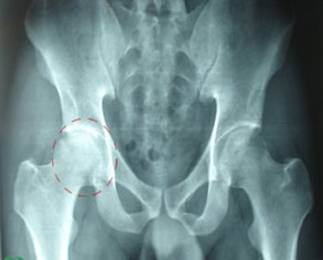

股骨頭壞死不容忽視

近日,骨關(guān)節(jié)外科門診接診了一名股骨頭壞死的患者,患者廖某因髖關(guān)節(jié)疼痛多年,行走后疼痛加重前來(lái)就診。股骨頭壞死在骨關(guān)節(jié)外科并不少見,輕者,疼痛時(shí)患者可以忍受,忍一忍就過(guò)去了。直到病情加重,才來(lái)醫(yī)院治療,往往延誤了治病的最佳時(shí)期。

股骨頭壞死,又稱股骨頭缺血性壞死,為常見的骨關(guān)節(jié)病之一。是由于多種原因?qū)е碌墓晒穷^局部血運(yùn)不良,從而引起骨細(xì)胞進(jìn)一步缺血、壞死、骨小梁斷裂、股骨頭塌陷的一種病變。